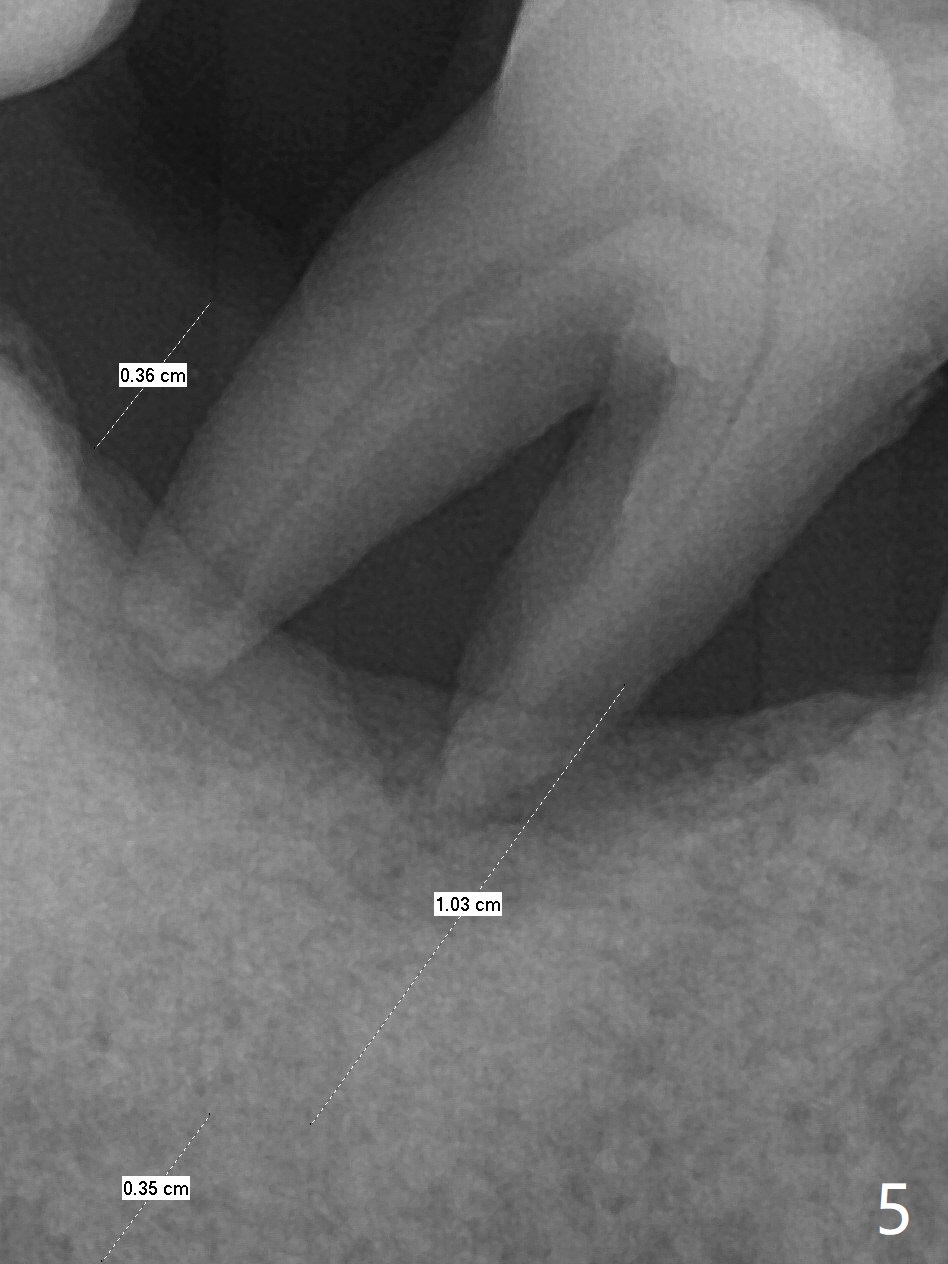

69岁男拔除左上5后右下6疼痛,要求拔除,骨质吸收严重,牙龈厚(图一:双箭头),其实后者是好事,血供好,植牙可以种植浅些(图二),周围放置骨粉(图三:红圆圈)。拍摄根尖片:近中牙槽窝种植与中隔种植,植体长度有优势(图五,四)。